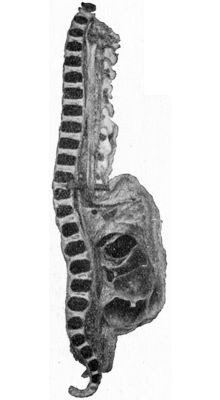

606 278.Larynx and Trachea surrounded by Goitre

607 279.Section of Goitre shown in

Fig. 278to illustrate Compression of Trachea